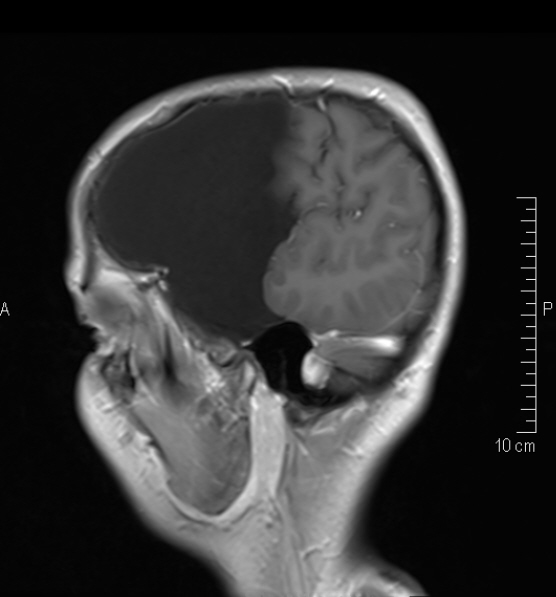

Hatte ja gesagt dass ich heute MRT Termin habe. Ich denke ich stell einfach mal von jeder Perspektiven Serie ein Bild ein und dann könnt ihr Euch selbst eine Meinung bilden ob gut oder schlecht. Einfach auf das Bild klicken, dann seht ihr es etwas größer.

Ich denke es ist nicht so ganz zu übersehen welches hier der schlechte Teil ist in meinem Kopf ist und das meine Hirnmittellinie alles andere als gerade ist. Und dass sich die ganze Sache im Vergleich zu letztem Mal auch noch mal wieder ein Stückchen mehr breit gemacht hat in meinem Kopf brauch ich wohl auch nicht so ganz zu erwähnen.